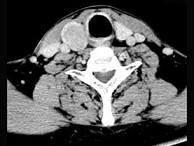

问题 男,43岁,因右颈部扪及一包块来院就诊。如图所示该患者应诊断为()

选项 A.甲状腺腺瘤 B.甲状腺腺癌 C.结节性甲状腺肿 D.甲状腺原发淋巴瘤 E.甲状腺转移瘤

答案 A